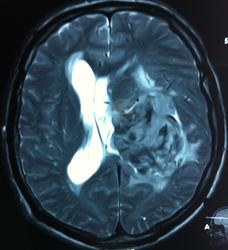

Начало вот здесь http://www.radiomed.ru/cases/kt-gms-obemnoe-obrazovanie-levoi-gemisfery-bolshogo-mozga-vnutrizheludochkovaya-meningioma. Пациент оперирован (меня сначала дезинформировали по поводу операции), перед операцией состояние ухудшилось, возникла правосторонняя гемиплегия, которая осталась и после декомпрессии. МРТ, КТ снимки и выписку предоставила супруга пациента, снимал на iphone, простите за качество, дисков с исследованиями не записывали. Надеюсь вопрос по данному случаю исчерпан.

Т2

И Вы считаете, что эта опухоль имеет интравентрикулярную локализацию?

Изначально по КТ я так предпологал, а теперь на 100% уверен, разве МРТ это не показало? Гистологически - менингиома, опухоль мозговой оболочки. Покажите, пожалуйста, образование где-нибудь прилежит к костям, где есть мозговая оболочка? Я не вижу, зато отчетливо вижу в левом боковом желудочке из оболочек сосудистого сплетения. Что вас еще смущает? По-моему, предостаточно фактов, чтобы развеять все сомнения.

Мне видится так. Иначе в данной локализации просто неоткуда расти оболочечной опухоли. На контрольной КТ, после декомпрессии, когда срединные структуры стали действительно срединны, правое обызвествленное сосудистое сплетение видно отчетливо, а левое, где оно? Ведь если бы образование компремировало, то после операции, когда часть мозга пролабировало в трепанационное отверстие мы бы увидели и левое сосудистое сплетение, но оно интимно связано с образованием и даже "потянулось" за ним в сторону декомпрессионного отверстия, потому что это и есть "росток" откуда выросла опухоль.

У меня вопрос (извините, если тупой - я-не волшебник, я только учусь=) - мне кажется, что в центре образования есть участки пустоты потока (сосуды), а разве менингиома склонна к такому неоангиогенезу? просто прочитала все вышенаписанное, вроде полностью согласна, но как вариант закралась мысль о сосудистой опухоли из сплетения бок.желудков. Если я совсем не права, прошу пояснить. Хочется все понимать уже на первых годах работы.) Заранее благодарю.